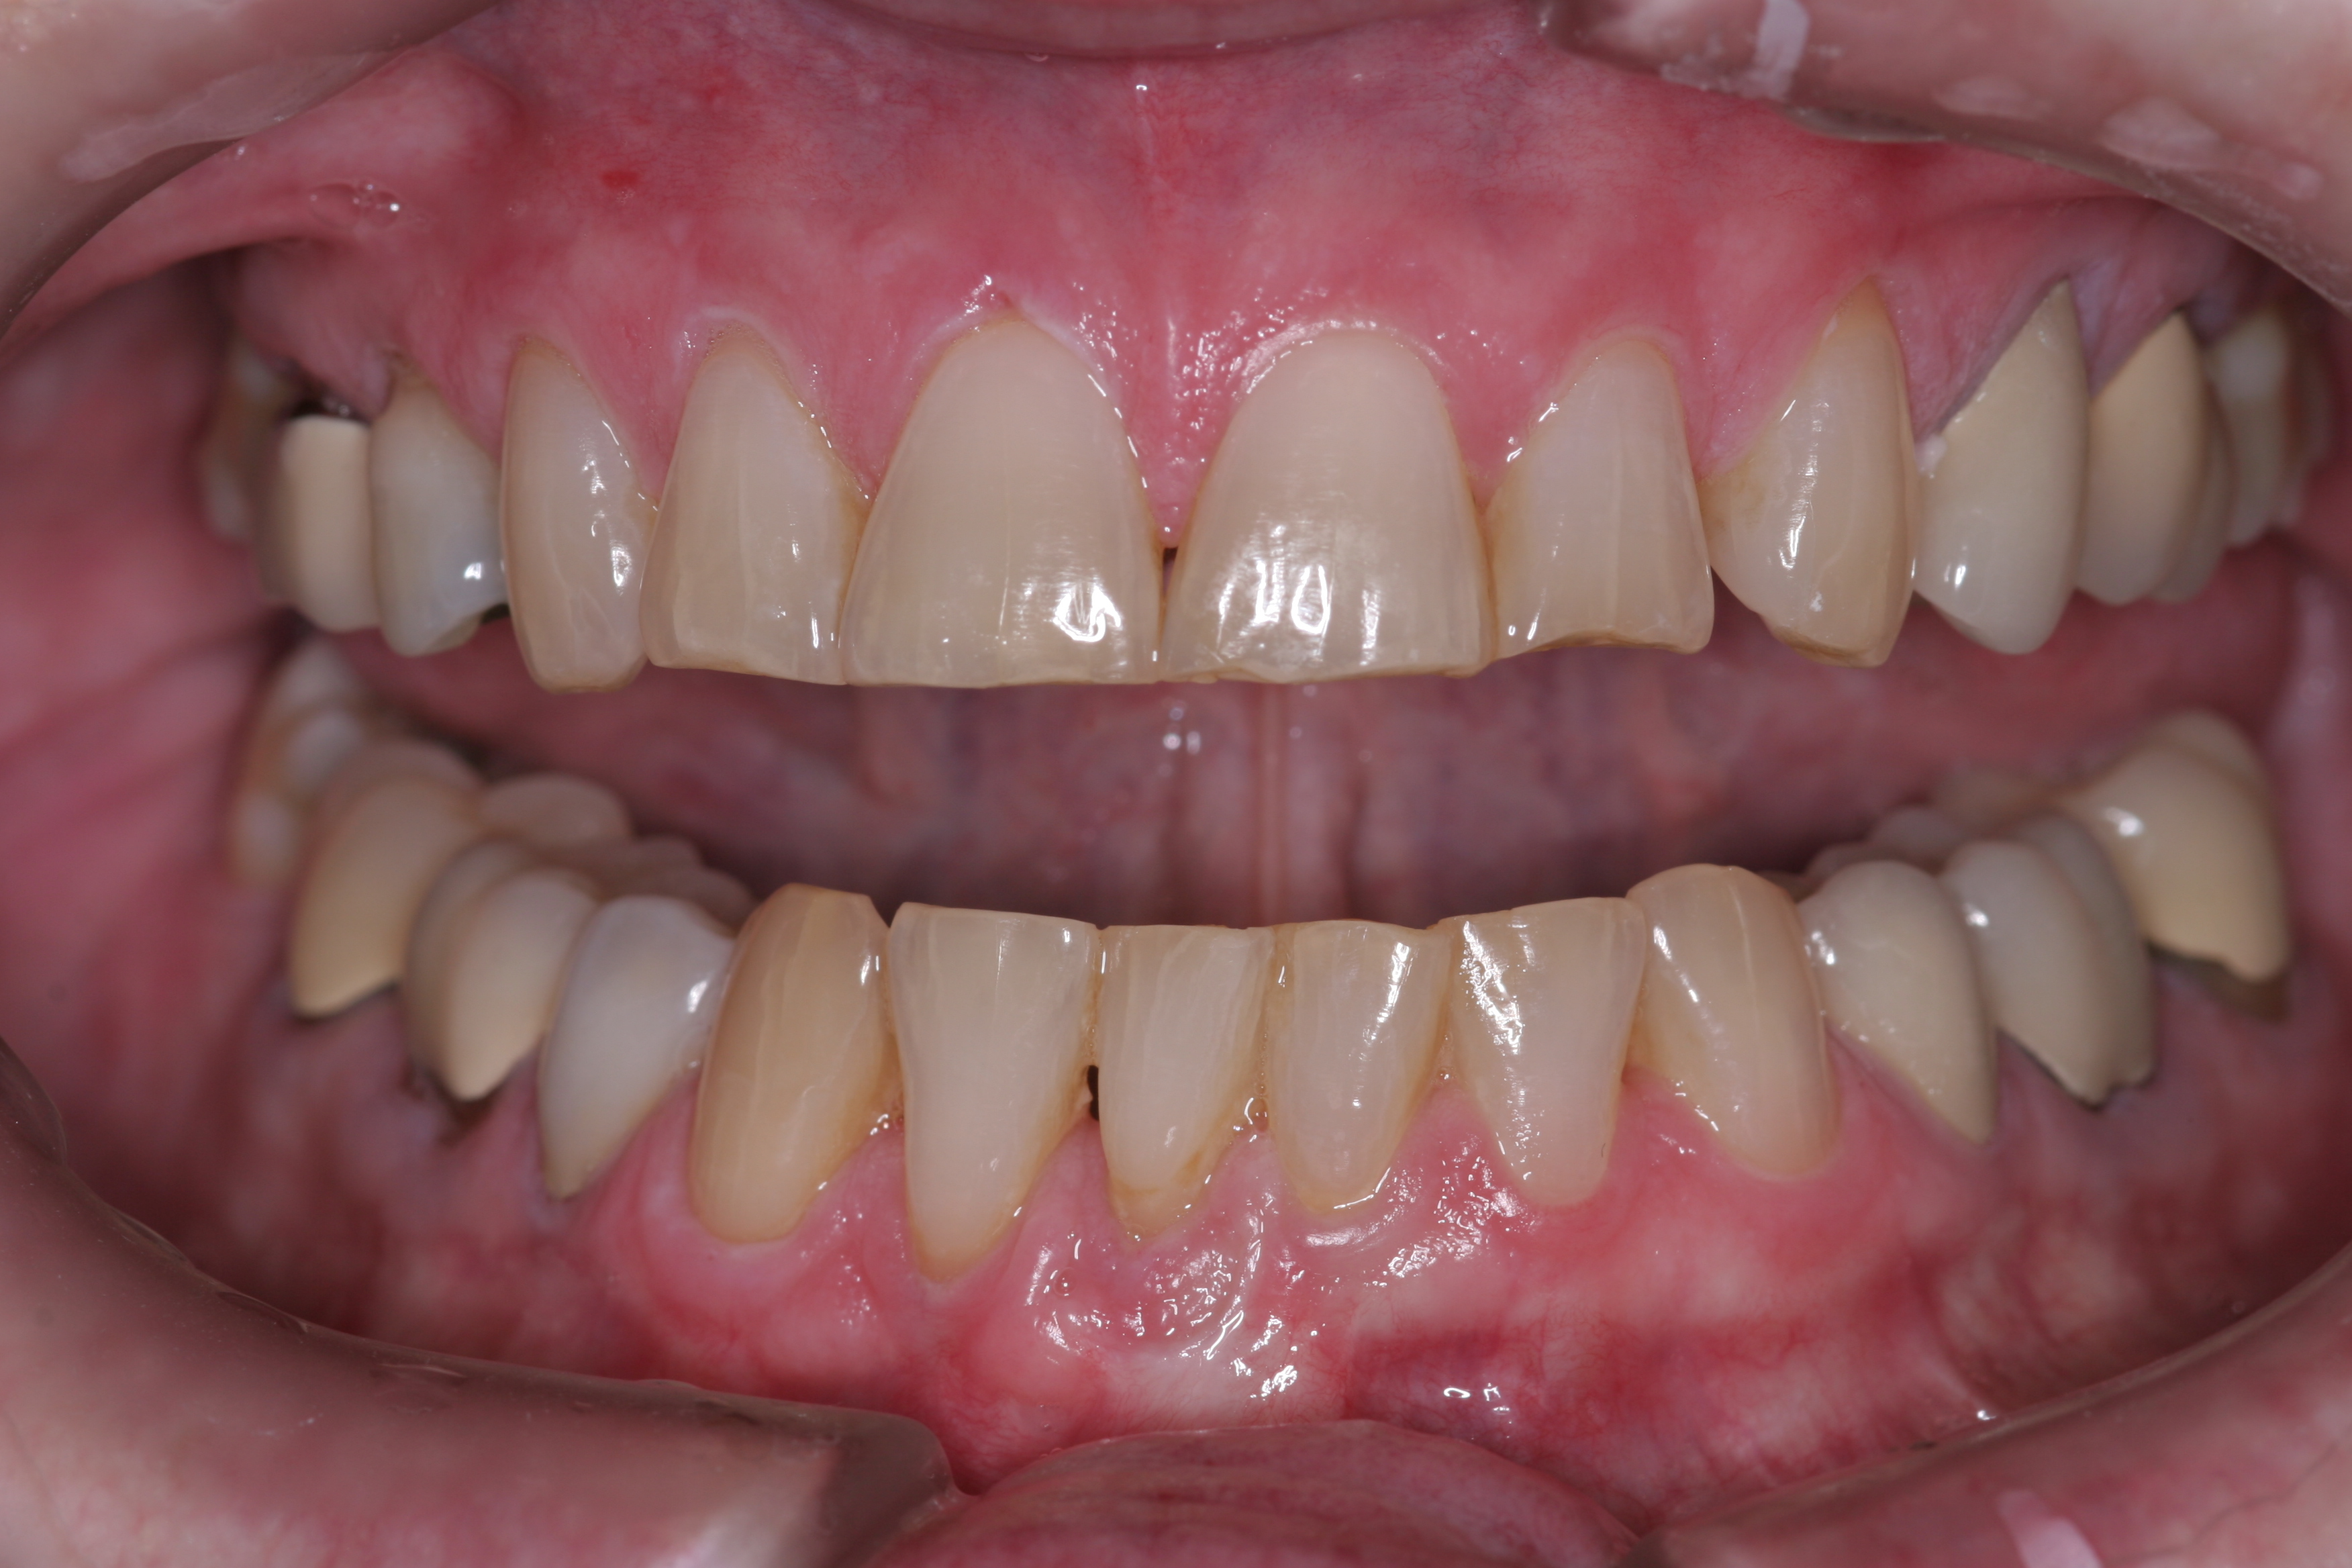

A patient presented with advanced generalized wear of her anterior teeth (Figure 10 and Figure 11). She was displeased with their overall appearance because of their color and wear (Figure 12). A complete examination was performed, revealing instability in her temporomandibular lateral poles bilaterally, sore muscles of mastication, advanced wear, a CR/MIP discrepancy, and loss of her anterior guidance due to the wear. Although the topic is beyond the scope of this article, the patient was also screened for possible sleep apnea. This included an evaluation of the Mallampati score, previous sleep therapy evaluation or treatment, snoring history, an evaluation of her neck size, her weight status, and the presence of the tonsils and their size. In every case, if this clinician suspects airway obstruction to be playing a role in tooth wear issues, the patient is referred to a sleep physician. The patient in this case displayed few apnea risk factors, and the patient’s anterior wear facets fit together like a “lock and key” pattern seen in parafunctional activity. Splint therapy was initiated to stabilize the joints and muscles. A repeatable CR position was verified through load testing. At this point diagnostic models, photographs, a CR bite record, and a facebow were taken and recorded.

(11.) A patient presented with advanced generalized wear of her anterior teeth, and was displeased with their overall appearance because of their color and wear.

Figure 11

(12.) A patient presented with advanced generalized wear of her anterior teeth, and was displeased with their overall appearance because of their color and wear.

Figure 12